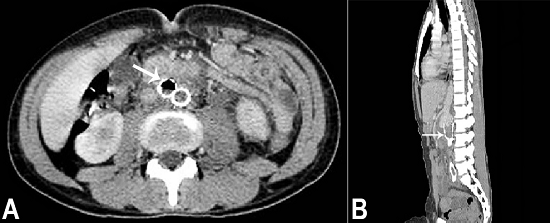

During his third hospitalization, the patient received 35 days of antimicrobial therapy, ran out of fever and refused to remain longer in the hospital. After 2 months he returned to the emergency facility complaining of severe and diffuse abdominal pain followed by upper digestive hemorrhage and hypovolemic shock. The abdominal CT revealed the presence of thrombi throughout the entire aorta and gaseous foci within the endoprosthesis indicating the presence of an aortoenteric fistula (Figure 3). Unfortunately, the patient died 1 day after hospital admission. An autopsy was performed with an informed consent signed by the family.